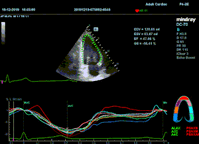

Всё изменилось с появлением технологии Speckle-tracking. Ультразвуковые приборы компании Mindray DC 8, 70, 80, Resona 6,7 оснащены данной функцией. Для использования необходим ЭКГ-канал. В чем же смысл данного технологического новшества? Прибор использует видео петли сечений миокарда, разбивает миокард на точки со стабильной визуализацией – speckle, и затем производит слежение каждой точки в течении нескольких сердечных циклов. Изменение пространства между точками дает нам представление о возможностях деформации миокарда, как продольной – Longitudinal Strain, так и деформации скручивания – торсии и Radial Strain.

Как работать с данным методом? Для Longitudinal Strain необходимо записать видео петли апикальных сечений в память прибора: 4С, 3С, 2С. Для повышения качества трекинга рекомендуется производить запись на выдохе пациента. Затем произвести разметку по линии эпикарда, перикарда и центра миокарда. Нажатием кнопки «начать слежение» активируется программный алгоритм, видео петля оживает вместе с размеченными точками-speckle’ами. При необходимости производится коррекция. После анализа всех трех сечений можно получить данных продольной деформации как в среднем значении, так и по каждому сегменту миокарда левого желудочка. Нормальным показателем считается Longitudinal Strain -20%. Нижней границей -14%.

Видео примеры на приборе Mindray DC 70